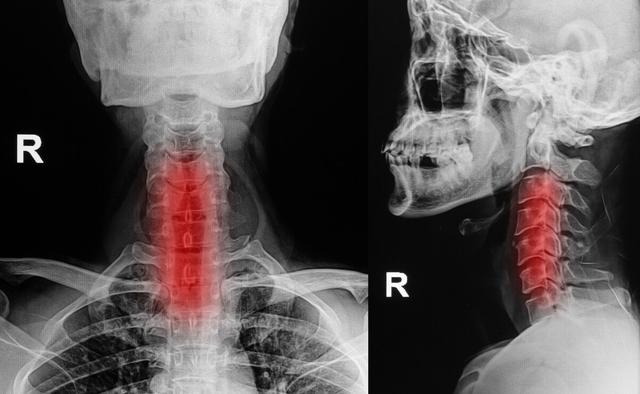

指の知覚神経は頸髄から神経根に分かれ、頸部腋窩で腕神経叢を形成し、上腕と前腕を通って橈骨神経、正中神経、尺骨神経となり、手と指に分布する末梢神経となる。

頚椎の変性や頚椎キーボードのヘルニアは神経根や脊髄を圧迫し、手指のしびれや痛みを引き起こし、時には運動機能にも影響を及ぼす。

頚椎症患者の種類によっては、指先のしびれも考えられる症状の一つですが、頚椎症患者は指先のしびれ以外にも、上肢や下肢の脱力感、首の後ろの痛み、歩行困難、耳鳴り、首の重苦しさ、めまい、吐き気などの症状を伴うことがあります。頚椎症の診断は難しくなく、整形外科に行ってレントゲン検査をすれば、はっきりした診断がつくかもしれません。

頚椎症、骨棘、椎間板ヘルニアなどは、脊髄から枝分かれする神経根が詰まりやすく、詰まると手のしびれも起こり、手のしびれは胸郭出口症候群と同じような症状が現れます。しかし、手のしびれによって引き起こされるこの症状は、より明らかな頚椎の不快感、こわばり、痛み、活動制限があるでしょう。

頚椎に問題がある場合、腕神経叢の神経が圧迫されると、手のしびれや手の痛みが生じ、脳への血液供給が不足し、めまいや吐き気を引き起こす深刻な引き金となります。頚椎症による手のしびれは、親指と人差し指のしびれ、小指と薬指のしびれなど、主に片側のしびれとして現れ、ボタンが結びにくい、箸が持ちにくいなど、指の柔軟性が失われます。頚椎症になると、手指のしびれだけでなく、頚部や肩の筋肉痛、上肢の放散痛などを伴うようになります。そのため、片側の手のしびれの症状が出たときには、頚椎症かどうかを警戒する必要があります。

5.頚椎症

頚椎症は頚椎が突出する長期的な要因により、両側の神経や血管を圧迫し、指のしびれの主な原因は神経から腕神経叢神経や頚神経を圧迫することであるため、腕神経叢神経損傷や頚神経叢神経損傷だけでなく、上肢の神経の損傷も指のしびれの原因となります。